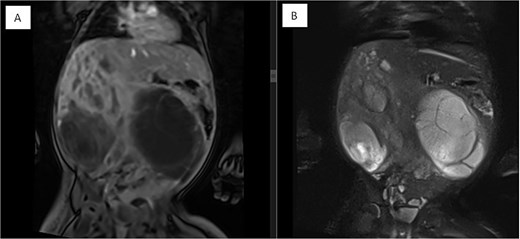

Several months later, she developed progressive abdominal distension and recurrent vomiting, prompting further evaluation. A CT scan of the abdomen revealed a large heterogeneous hepatic mass primarily occupying the right lobe, measuring 12.6 × 8.8 × 14 cm, with multicystic areas and soft tissue enhancement. MRI also demonstrated a large right hepatic lobe mass with mass effect and heterogeneous enhancement (Figs 1 and 2). Mild upper abdominal lymphadenopathy was noted (largest node 8 × 10 mm), along with a right-sided inguinal hernia. Differential diagnoses included HMH, with hepatoblastoma and undifferentiated sarcoma considered less likely. A chest CT showed mild pericardial effusion and an inflammatory appearance.

Coronal MRI images of the abdomen showing a mass effect in the right hepatic lobe. (A) Coronal T1 post-contrast and (B) coronal T2 HASTE FS images demonstrate spatial relationships, including compression of the right kidney, pancreas, and major vessels, with no invasion. The mass displaces bowel loops inferiorly and causes an anterior abdominal wall bulge.